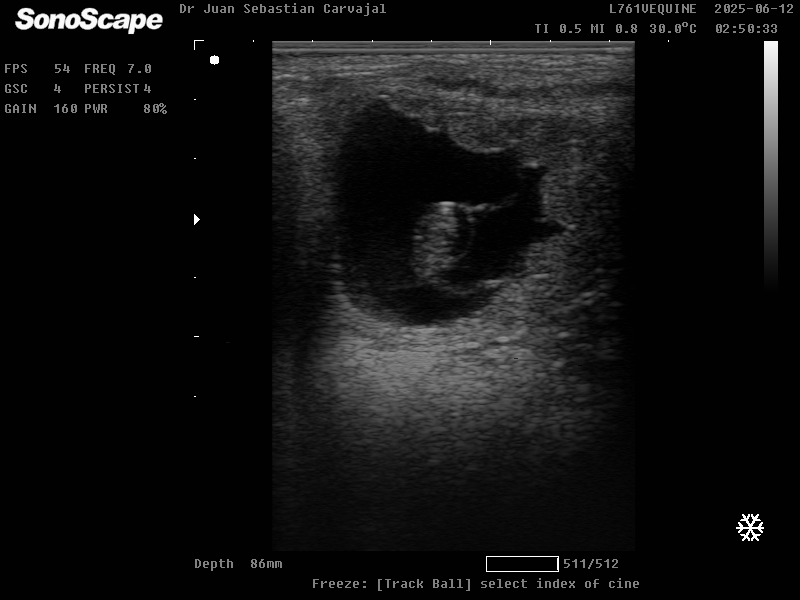

Dx de gestación